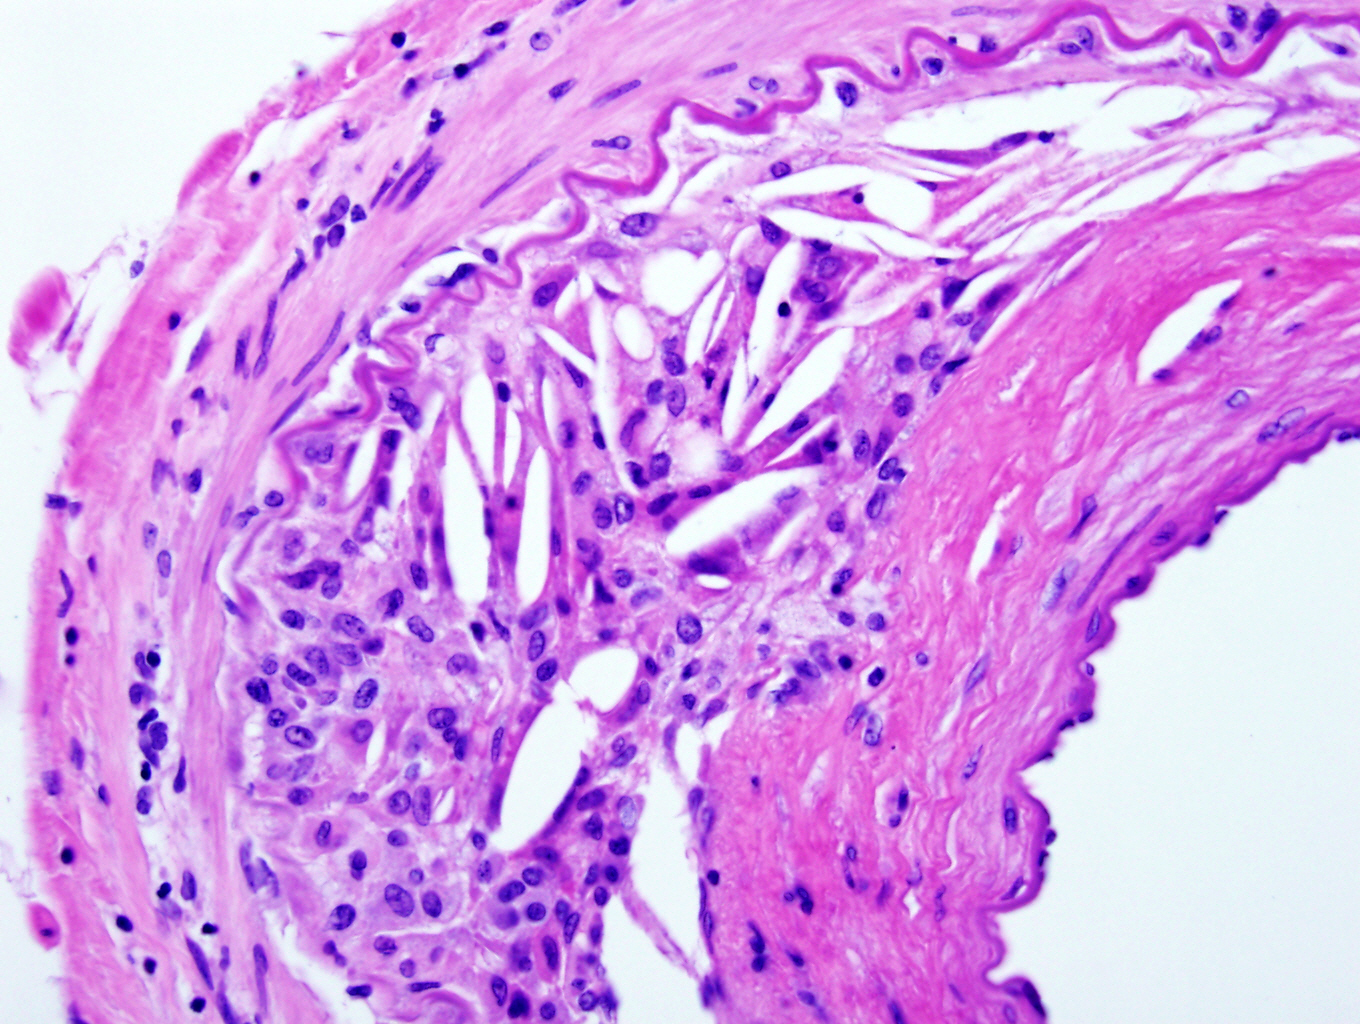

Microscopic (histologic) description

- Fibrous cap atheroma (Am J Med 2009;122:S3):

- Well formed necrotic core with overlying fibrous cap; smooth muscle cells, macrophages, lymphocytes and connective tissue components may be present

- With rupture: luminal thrombus communicates with underlying necrotic core

- Fibrocalcific plaque: collagen rich plaque, contains large areas of calcification with few inflammatory cells, necrotic core may be present

Microscopic (histologic) images